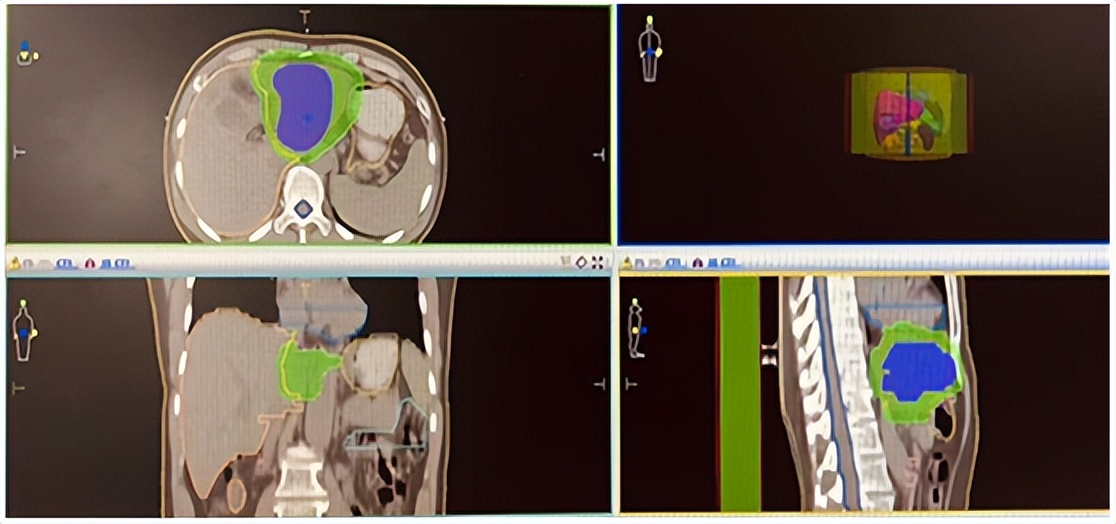

经院内多学科会诊讨论后,评估了王先生当时的病情是无法做根治性手术的。治疗方案是,先进行二周期化疗联合免疫治疗,再进行肝脏病灶大分割精准放疗,PGTV:5Gy*8f,PTV 3Gy*8f(见下图)。经过治疗,王先生复查肿瘤标志物CA199明显降低,影像学检查可见病灶逐步缩小。